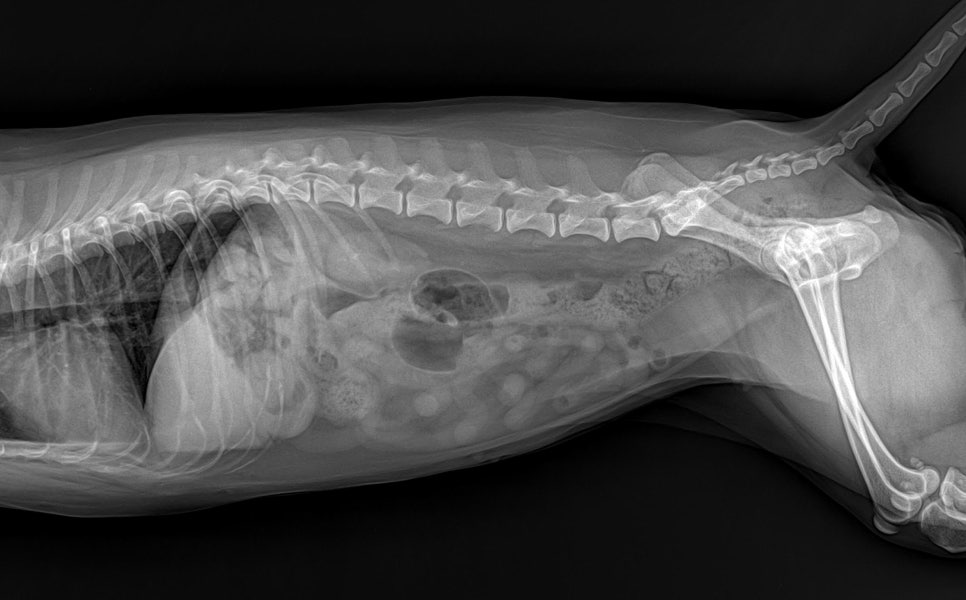

시술 과정에서 발치가 필요할 정도의 치아 손상은 관찰되지 않았으며, 스케일링과 이후의 지속적인 구강 관리로 충분히 관리 가능한 단계였습니다. 환자는 전신마취 하에 안전하게 스케일링을 마쳤고, 회복 과정에서도 안정적인 상태를 유지하였습니다.

환자 스케일링 완료 사진 / 출처: 라온동물메디컬센터